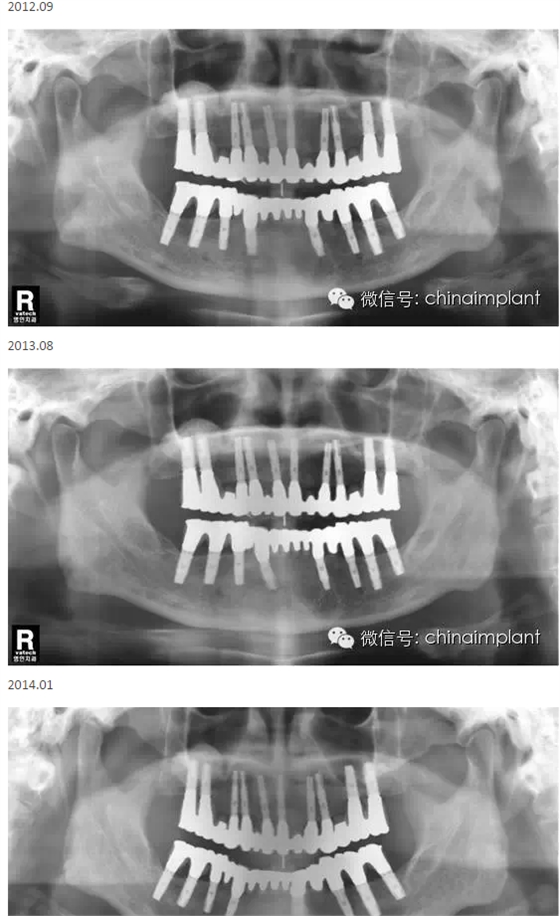

本案例已經(jīng)將近10年了(2005年12月),但是修復(fù)效果個(gè)人認(rèn)為很不錯(cuò),所以拿出來和大家分享。

從修復(fù)全景片上看到牙齒排列非常好